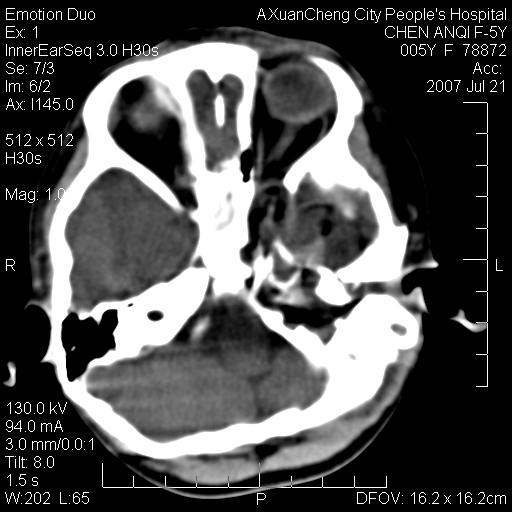

患儿5岁,左耳流脓痛疼一周,左外耳道肉芽组织填塞 软组织窗显示病灶内结节状低密度影为气体密度

1.左耳中耳炎. 2.考虑伴颅内感染.

颅底骨质破坏,建议增强扫描

感觉不象恶性的

补充:腺样体肥大.